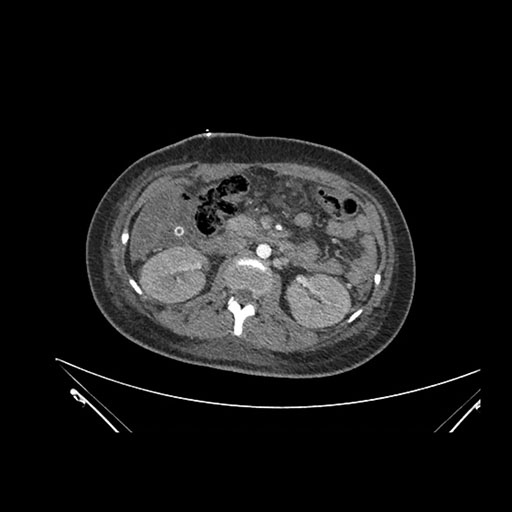

Axial Venous

Imaging analysis

Based on initial findings, which issue(s) would you be most concerned about?